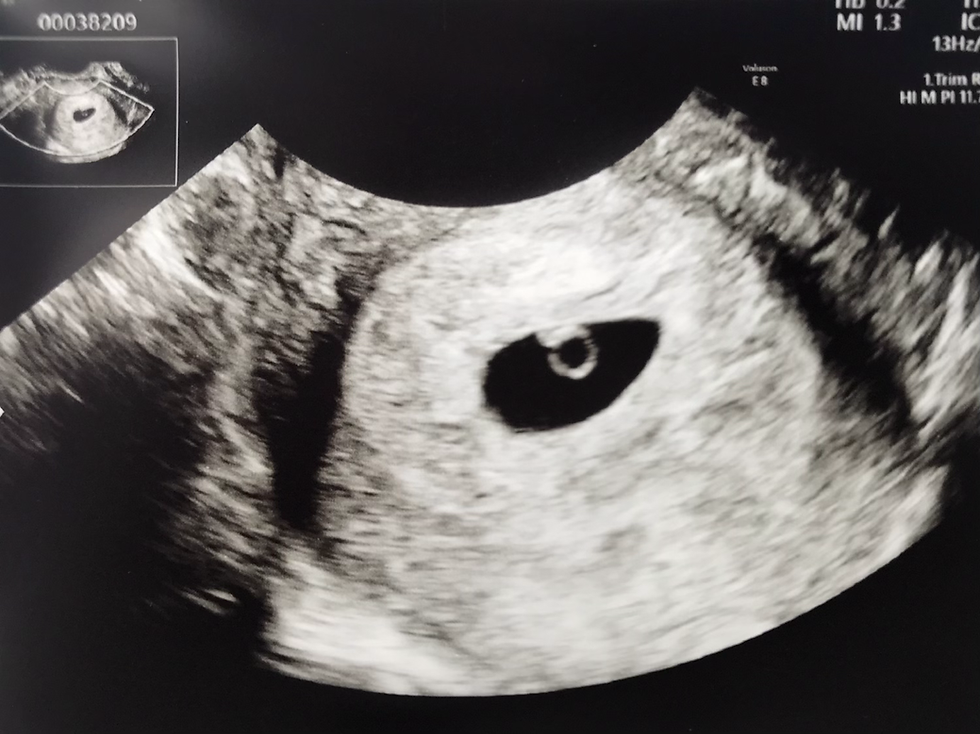

(がっちゃんの初めてのエコー写真☆)